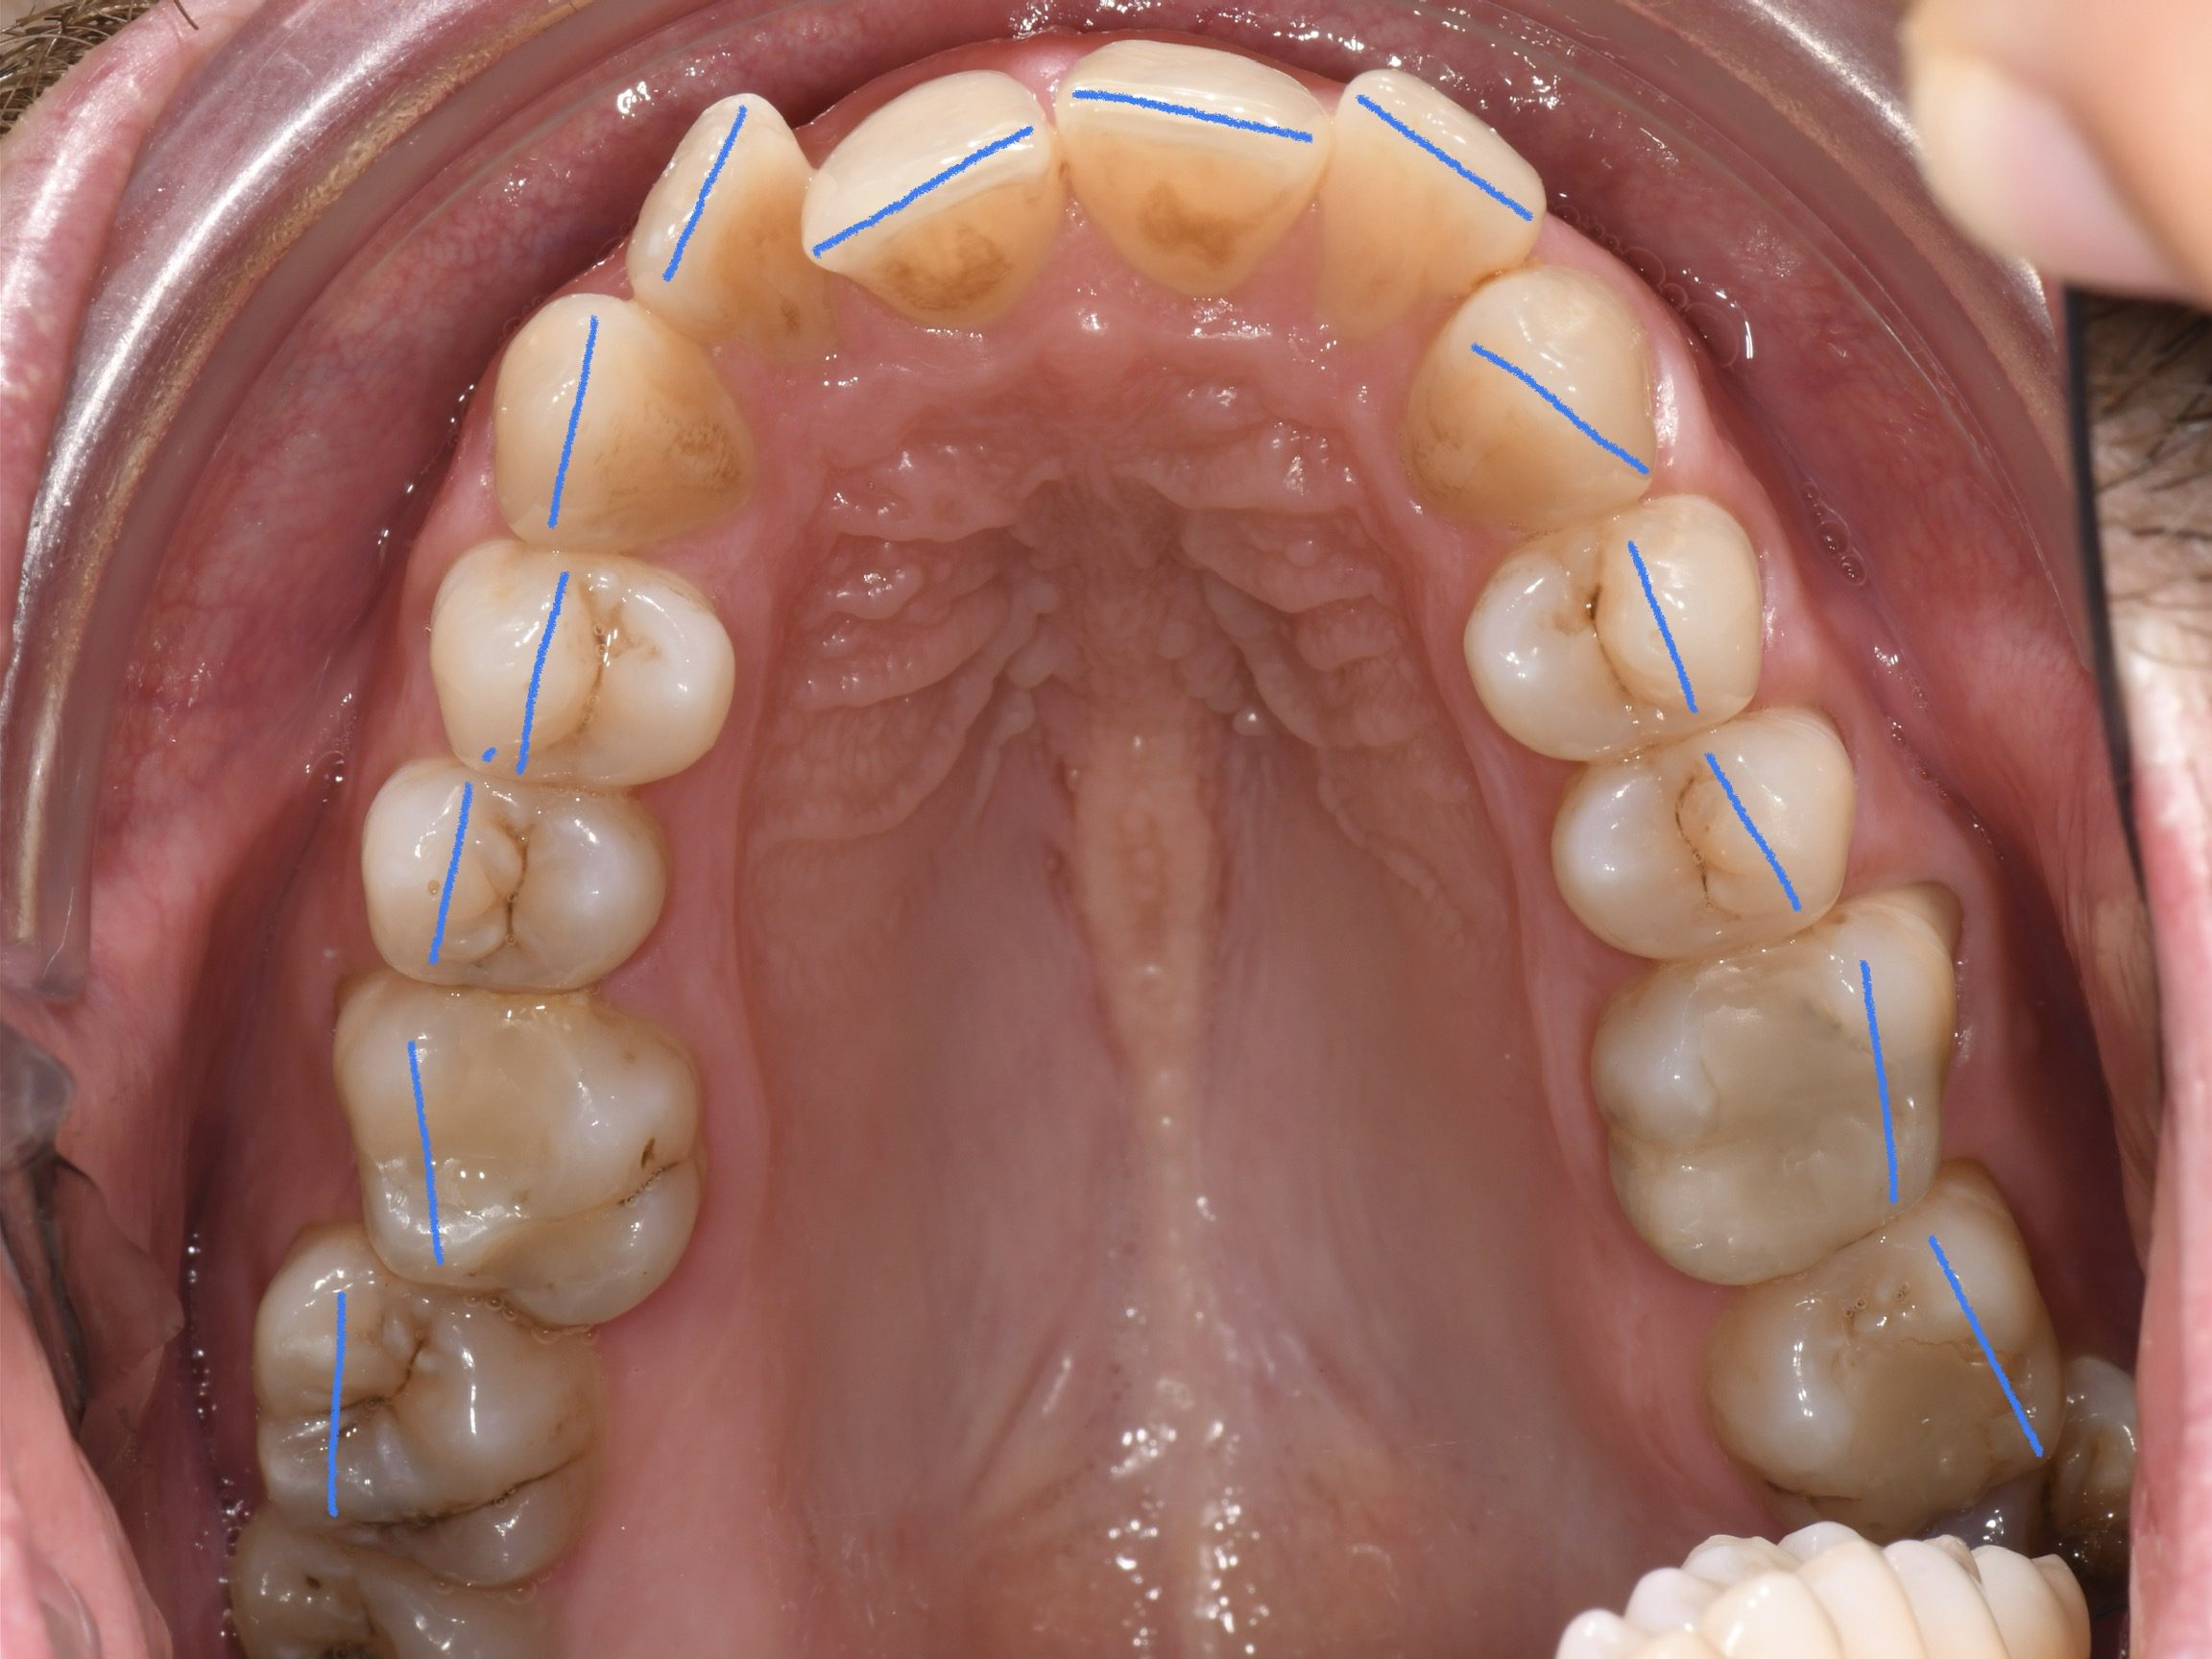

Az elmúlt évekből rengeteg szakmai referenciát tudnánk bemutatni, amelyek különböző fogszabályozási problémákat oldottak meg. Válogatva a több száz esetből, ezen az oldalon olyan képeket, információkat igyekeztünk bemutatni, amelyeknek a segítségével a jövőbeni pácienseinknek azt tudjuk üzenni: A Te fogsorod is lehet gyönyörű!

(Képeket a Pácienseink külön írásos beleegyezésével mutatjuk be!)